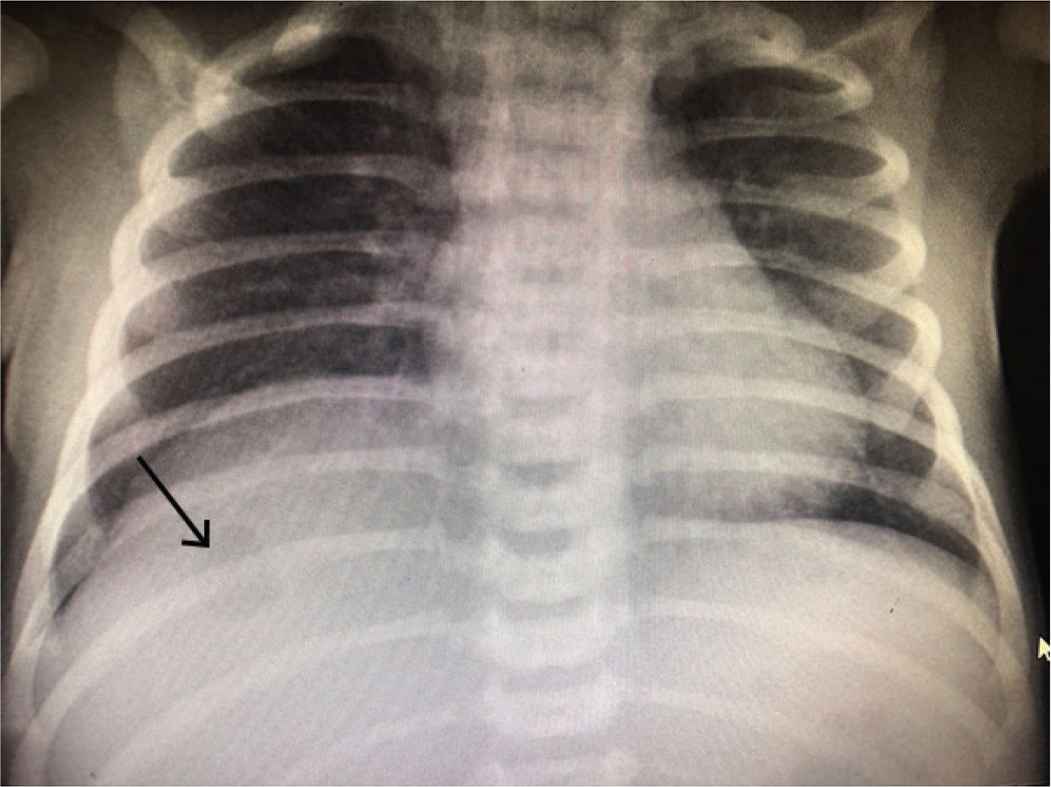

A 16-day-old term, male baby, birth weight 3.1 kg, was transferred to our NICU with sepsis. The Blood Culture and Sensitivity (C/S) was persistently positive for coagulase-negative staphylococci. He was born in the referring hospital by spontaneous vaginal delivery and admitted to their NICU due to meconium aspiration syndrome. He required ventilation for 1 week and an Umbilical Venous Catheter (UVC) was placed in the portal vein at birth. The UVC remained in this position for 6 days with Total Parenteral Nutrition (TPN) running through it. A chest drain was required for right pneumothorax. On admission to our hospital, he had hepatomegaly with raised C-Reactive Protein (CRP). Abdominal X-ray showed enlarged liver with high right-side diaphragm and a small 1 × 1 cm2 air bubble in the liver Figure 1. Abdominal US showed a heterogeneous multiloculated collection in the right liver lobe indenting the right hemidiaphragm, suggestive of liver abscess. Abdominal computed tomography (CT) showed a large multiloculated hepatic abscess with its main bulk in the right hepatic lobe with upper subcapsular extension causing right diaphragmatic elevation and showing multiple air loculi inside suggesting anerobic infection Figure 2A and 2B. The abscess was drained by an emergency laparotomy and an indwelling drain was placed. The C/S from pus was negative, while biopsy from the abscess wall showed nonspecific acute and chronic inflammation with granulation tissue. CRP gradually normalized, the drain was removed, and the baby recovered very well.

Thoracic and abdominal X-rays showing gas bubble in the liver.

The clinical presentation and laboratory findings of neonatal liver abscess are usually nonspecific; similar to those of generalized sepsis. Hepatomegaly and raised diaphragm on X-rays point towards a possible space-occupying mass in the liver. A high index of suspicion should always be raised in a baby with potential risk factors. Abdominal US is usually the first investigation that can detect, locate, and define a liver abscess [7]. US has a sensitivity of 80–90% in screening and diagnosis of neonatal liver abscess. US can also help in screening associated abscesses in other organs, such as spleen, kidney, and lungs. Being a low cost, noninvasive, mobile, and easily available instrument, US is useful for diagnosis and monitoring of response to treatment; both surgical and medical. Serial US done at frequent intervals during the course of the disease gives useful information on the progress of the healing process. US can also be used to guide percutaneous drainage of neonatal liver abscess. US findings of neonatal liver abscess may be similar to those of hepatoblastoma, infantile hemangioendothelioma, and hepatic hamartoma. Serum α-fetoprotein levels may be helpful in differentiating these malignant and benign hepatic masses from liver abscesses [2]. Abdominal CT (with and without contrast) gives a firm diagnosis and also defines the extent, structure (single or multiloculated), and any connections with the UVC or central lines. Typical CT appearance is that of a well-circumscribed, low-attenuation mass with a contrast-enhancing rim. Together, abdominal US and CT scan constitute the most sensitive diagnostic tests in the detection of neonatal liver abscess [8]. A raised diaphragm is the only useful sign on plain thoracic and abdominal X-rays. Our case was unusual because the clinical suspicion was raised after seeing a large gas bubble in the liver substance Figure 1. This could have been caused by a gas-producing organism, although pus culture was negative. This was not a surprise because, prior to surgery, our baby had received antibiotics for several days.